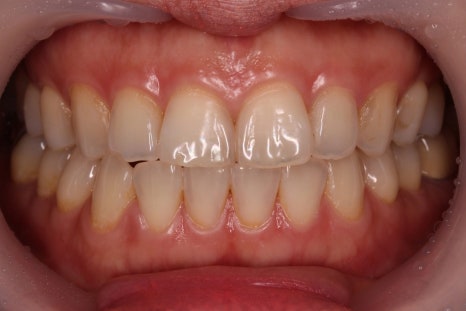

"저는 앞니부터 어금니까지 총 24개의 미니쉬를 받았어요." 안녕하세요. 미니쉬치과병원 원장 이정은입니다. 미니쉬를 받은 지 앞니는 벌써 3년, 어금니는 어느덧 6년쯤 됐네요. 평소에는 미니쉬를 했다는 걸 잊고 지내는데요. 그러다 환자분들이 "원장님도 직접 하셨나요?" 하고 물어보실 때마다 '아, 맞다!'...

"저는 앞니부터 어금니까지 총 24개의 미니쉬를 받았어요."

미니쉬를 받은 지 앞니는 벌써 3년, 어금니는 어느덧 6년쯤 됐네요.

“네! 이게 바로 미니쉬한 제 치아예요.”

의사인 제가 직접 미니쉬를 경험했고, 지금도 정말 만족하며 잘 쓰고 있다는 사실 하나만으로도 환자분들은 안심하고 신뢰를 하시더라구요.

어금니 미니쉬를 받은 후 위에 8개, 아래에 10개, 총 18개의 앞니 미니쉬도 진행했죠.

결과적적으로 치아의 기능은 안정되었고 심미적으로는 훨씬 자연스러워졌어요.

지금은 교합도 편안하고 자신 있게 웃고 있답니다.